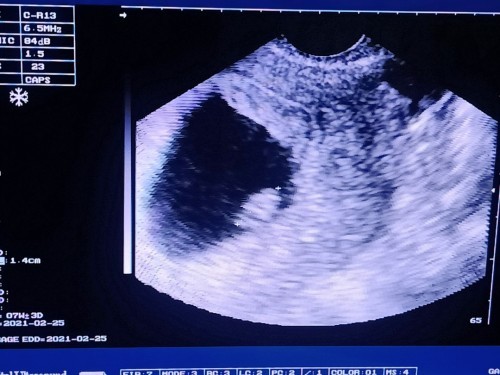

7 Weeks and 3 Days

Sino pong almost 8Weeks palang dito? Hello April Babies! ♥️♥️ Share ko lang, Sobrang liit pa pala ni Baby no? Pero may heartbeat na sya. Nakakaramdam ako ng mild cramps pero it's normal lang pala basta mild lang. Thanks God at normal ang trans V result ko. Keep safe po sa lahat! ♥️ Godbless Us

Congrats, mommy! Ganyan lang din nakita ko nung nagpa-transv ako nung 8 weeks. Parang peanut lang si baby. Kaka-transv ko lang ulit last Friday (12 weeks) and mas malaki na si baby. May arms & legs na rin. Ang sarap sa feeling na may growing baby tayo sa tummy 💞